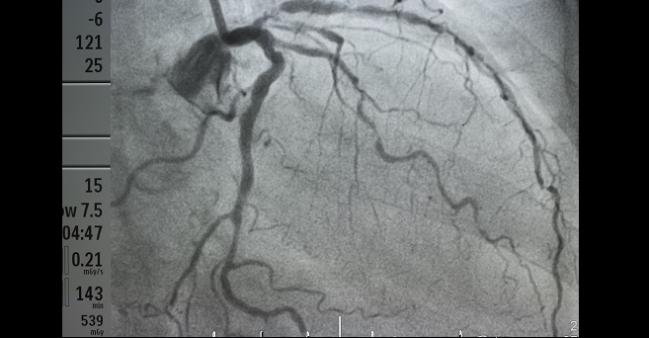

The presence of multivessel disease should prompt clinicians to consider longer-term ticagrelor in their post-MI patients, a new subanalysis of the PEGASUS-TIMI 54 trial suggests.

“We know that atherosclerosis is a systemic disease, and one important observation from this paper is that patients with multivessel disease, even if they've been stented, are still at very high risk,” Bonaca continued. “Most clinicians know that [but] just simply knowing when a patient has their MI if they've had multivessel disease can be an important in terms of determining the optimal intensity and duration of [dual antiplatelet therapy (DAPT)].”

For this prespecified analysis of the trial, published in the February 6, 2018, issue of the Journal of the American College of Cardiology, Bonaca along with Sameer Bansilal, MD, MS (Icahn School of Medicine at Mount Sinai, New York), and colleagues found that risk of ischemic events was significantly higher among patients with multivessel disease (59.4% of the cohort) than among those without. For the composite primary endpoint of MACE (cardiovascular death, MI, and stroke) that difference was 9.37% versus 8.57% (adjusted HR 1.24; 95% CI 1.03-1.50) and for coronary events it was 7.67% versus 5.34% (adjusted HR 1.49; 95% CI 1.19-1.87).